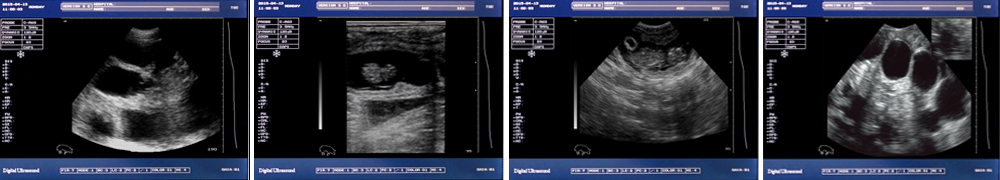

● 顯示模式:B、B/B、B+M、M、4B;

一流的數字成像技術 圖像更清晰